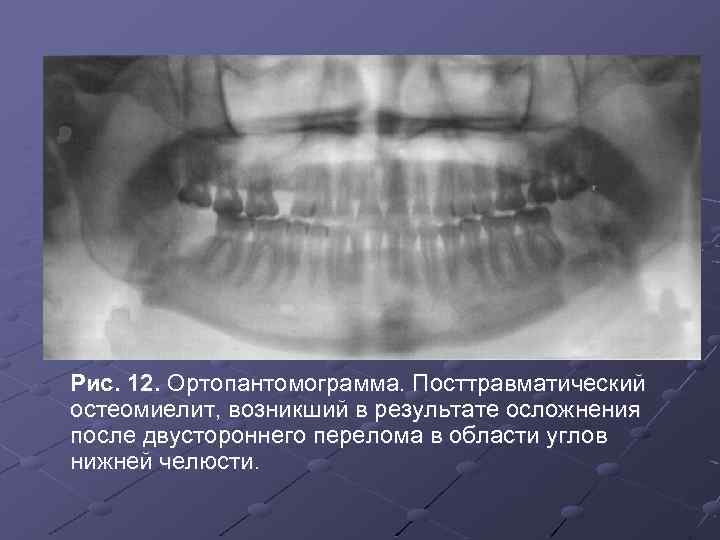

Рентгеновские снимки посттравматического остеомиелита челюсти: Медицинские случаи

Раздел: Образы вокруг